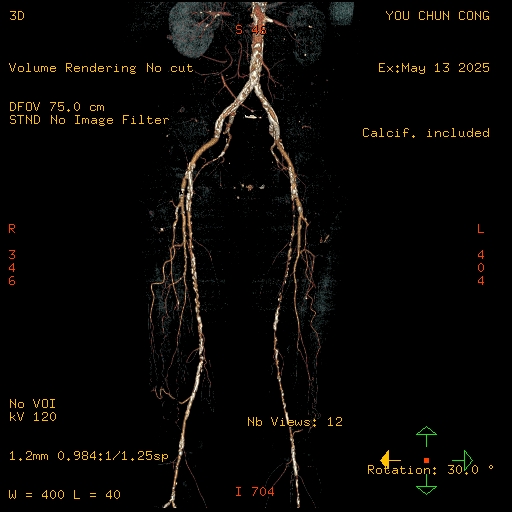

Relevant Test Results Prior to Catheterization

Peripheral angiogram showed diffuse atherosclerosis and multiple critical stenosis of bilateral ATK artery. Considering the patient's chief complaint was right leg tenderness, PTA for right leg was performed.